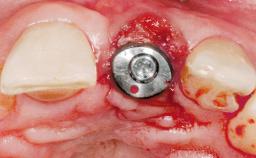

Immediate Flapless Placement of an Implant in a Maxillary Left Central Incisor Site

A 42-year-old female patient was referred to our clinic at the School of Dentistry of the University of São Paulo in November 2004, presenting a deficient restoration in the upper left central incisor. The clinical examination revealed no gingival retraction or any signs of gingival inflammation and, therefore, previous periodontal treatment was not considered. The patient presented a high lip line at full smile and a thin tissue biotype. This combination characterized a high-risk situation from an anatomic point of view, which required careful preoperative planning and cautious surgical execution.